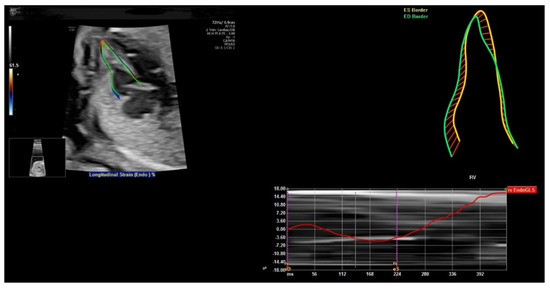

6. FetalHQ